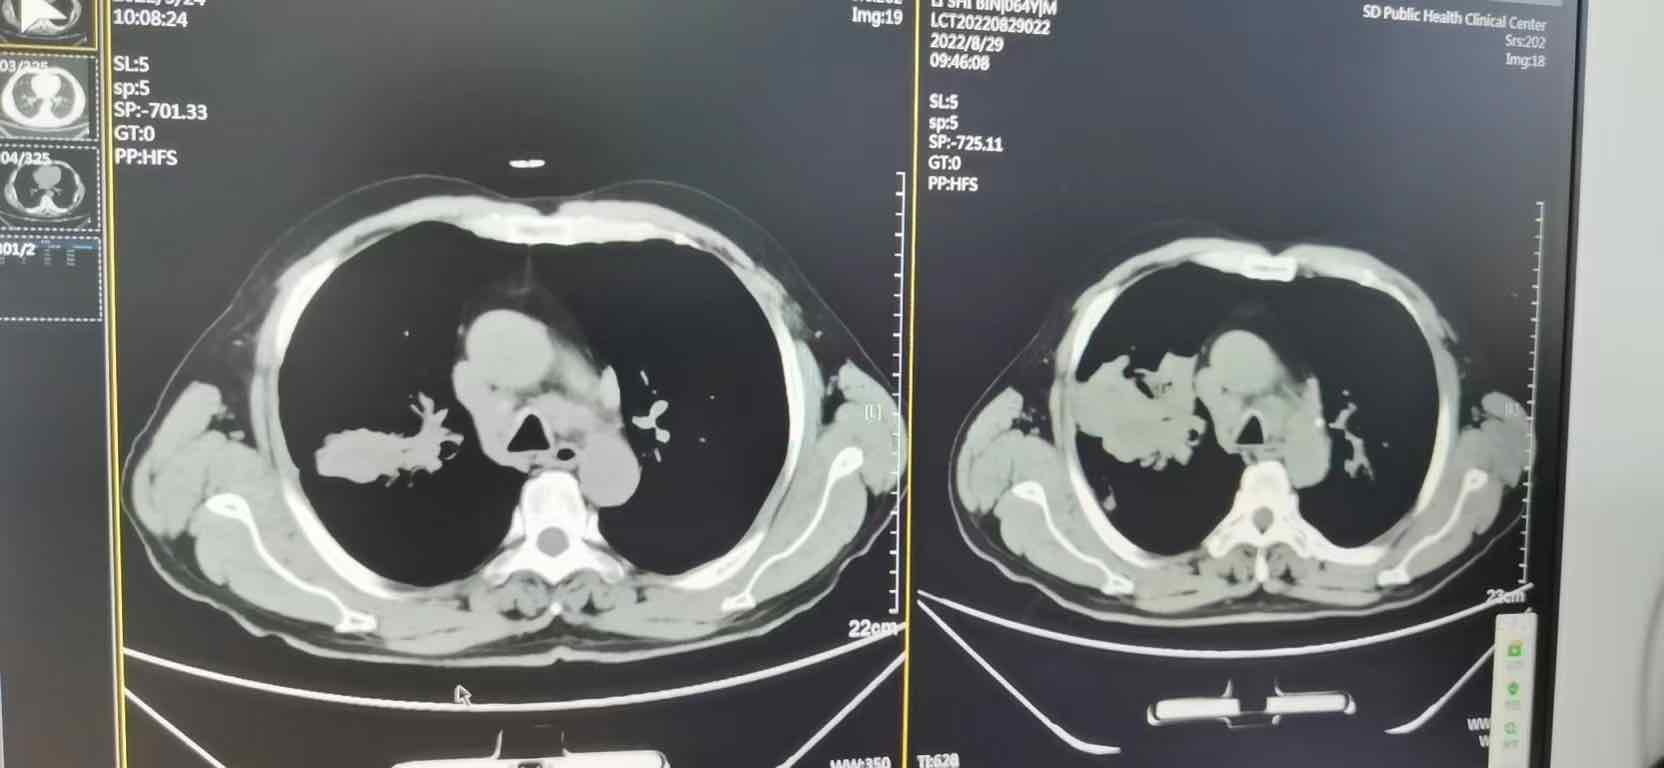

9月25日CT显示吸收明显,继续第三次OY联用

以下是近一个月CT变化(左面为最新),开始起效后,效果显著而快速。

本次方案去掉白紫(老爸化疗反应大,腿痛,发烧,食欲不振),方案为培美+O+Y+贝伐